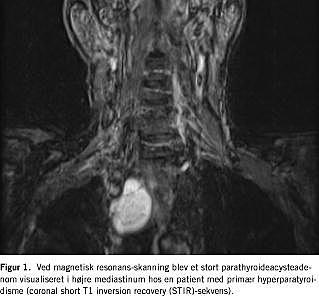

Femten dage postoperativt blev patienten genindlagt med træthed, muskel- og ledsmerter. Plasma Ca2+ var 2,40 mmol pr. l, PTH 1.097 ng pr. l og kreatinin 350 μmol pr. l. Parathyroideascintigrafien blev gentaget, men uden positivt fund. Patienten blev henvist til magnetisk resonans (MR)-skanning. En cystisk proces (4 × 5 cm) blev erkendt visuelt i øvre højre mediastinum (Figur 1 ), samme sted som den halscyste, der ved operationen blev punkteret. En endoskopisk ultralyd-skanning med guided cysteaspiration blev foretaget. PTH-koncentrationen i cystevæsken blev målt i forskellige fortyndinger med divergerende resultater, men konklusivt var koncentrationen meget høj og væsentligt højere end koncentrationen i patientens plasma.

Omkring 30 tilfælde med mediastinale PTH-producerende parathyroideacyster er beskrevet i litteraturen [2]. Hormonproducerende parathyroideacyster kan være resultatet af en cystisk degeneration af et eksisterende parathyroideaadenom [4]. I denne sygehistore blev cysteadenomet ikke erkendt visuelt ved scintigrafi, formentligt fordi adenomet kun bestod af en smal bræmme af parathyroideavæv omkring selve cysten. Derimod var MR-skanning velegnet med henblik på diagnostik. Generelt er MR-skanning ikke førstevalg ved lokalisationsbestemmelse af parathyroideadenomer, men ved ektopisk lokaliserede adenomer er det en meget velegnet teknik [5].